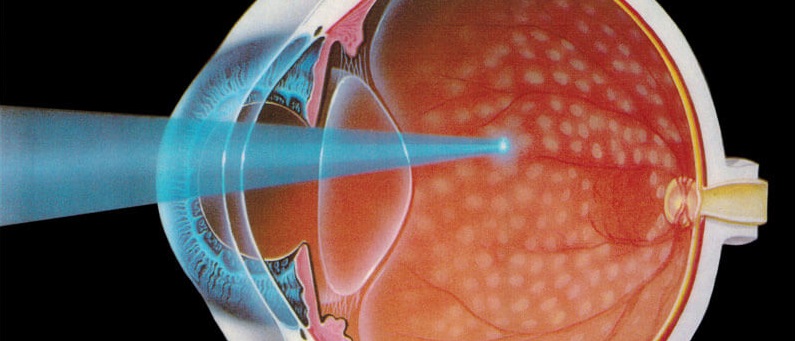

Laser Treatment

Retinal laser involves a green light which is passed on to the retina using a contact lens applied on the eye. This is a painless procedure with no side effects. The procedure takes about 5 minutes in most cases. The light produces a very small burn on the retina in a process called photocoagulation.

In diabetic retinopathy pan retinal photocoagulation is done. This involves treating the entire avascular retina with laser. While many hospitals do this in 3 separate settings, our advanced technology has allowed this to be completed in a single sitting in most patients. Laser helps to divert blood flow to the healthy retina while treating the unhealthy retina. This is required for advanced cases of diabetic retinopathy and vein occlusions involving retinal avascularity. If not done in time, the new vessels growing on the retina can bleed causing vitreous hemorrhage.

Laser is also required for retinal holes and tears. In this case the weak area on the retina is surrounded with laser spots which produce burns, fencing off the area. This prevents a major complication called retinal detachment.